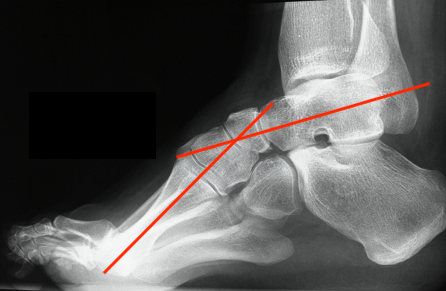

X-ray

Meary's angle

- longitudinal talus axis - 1st metatarsal angle

- normal 0o

- cavus > 20o